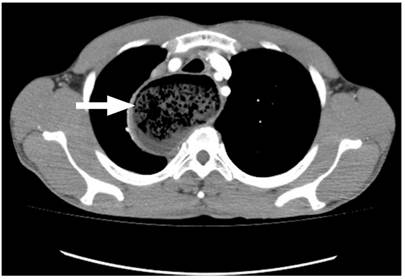

Hombre de 42 años, conductor, sin antecedentes de importancia, quien consultó por un cuadro de 3 años de evolución de disfagia progresiva inicialmente para sólidos y luego para líquidos, y regurgitación; con un aumento de los síntomas en los últimos 4 meses, se asocia con pérdida de 15 kg de peso (Eckardt 9). Al ingreso tenía signos de desnutrición grave y halitosis, sin disnea, adenomegalias periféricas, visceromegalias o ascitis. Se pasó una sonda nasogástrica y se obtuvo un drenaje alimentario abundante. Se realizó una radiografía de tórax en la que se registró una aparente masa mediastinal que desplaza la línea media (Figura 1). Ante este hallazgo y tos seca persistente, se complementa con una tomografía axial computarizada (TAC) de tórax con contraste, en la que se reportó megaesófago y hallazgos sugestivos de acalasia, sin poder descartar un compromiso neoplásico en la unión gastroesofágica (Figura 2).